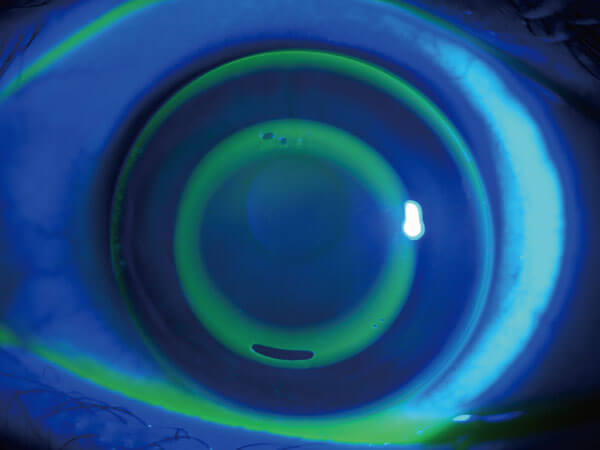

醫療設施:角膜塑型片驗配

高度近視高度散光或角塑片更換 使用全球最高品質美國歐基里德Euclid角膜塑型片。 #建議售價: 2萬6起,依度數及散光有所不同。